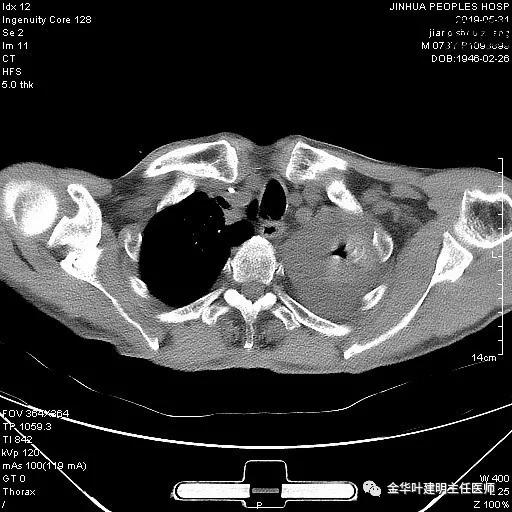

术前检查冠脉CT示:左冠前降支近段多发钙化斑块伴管腔重度狭窄(约85%),建议DSA检查。但追问病史以往平时无胸痛或胸闷症状,运动试验提示可疑阳性(上斜型压低),活动后胸闷气闭症状不明显,既往否认高血压、糖尿病。所以经过心内科会诊讨论,认为还是可以进行手术。术前冠状动脉CT示: